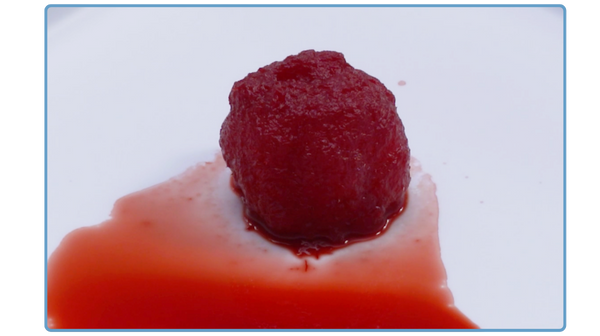

Optimized Handling

The interlocking fiber microhooks in PliaFX grafts provide optimized handling characteristics.4,5,7,8† The fibers interlock to provide a moldable, intact graft that easily transfers to the surgical site, conforms to the surgical site, and resists migration.4